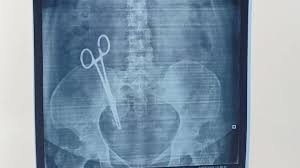

ವೈದ್ಯರ ನಿರ್ಲಕ್ಷ್ಯದಿಂದ ಮಹಿಳೆಯೊಬ್ಬರು ಸುಮಾರು 17 ವರ್ಷಗಳಿಂದ ಹೊಟ್ಟೆನೋವಿವಿಂದ ನರಳಿದ ಘಟನೆ ಯುಪಿಯ ಲಖನೌದಲ್ಲಿ ನಡೆದಿದೆ.ಸಂಧ್ಯಾ ಪಾಂಡೆ ಎಂಬ ಮಹಿಳೆ ಹೊಟ್ಟೆ ನೋವಿನಿಂದ ಫೆಬ್ರವರಿ 28, 2008 ರಂದು ಶೀ ಮೆಡಿಕಲ್ ಕೇರ್ ಆಸ್ಪತ್ರೆಗೆ ದಾಖಲಾಗಿದ್ದರು.

ಆಕೆಗೆ ಸಿ-ಸೆಕ್ಷನ್ ಆಪರೇಷನ್ ಮಾಡಿದ್ದ ವೈದ್ಯರು ಕತ್ತರಿಯನ್ನು ಹೊಟ್ಟೆಯಲ್ಲೇ ಮರೆತಿದ್ದರು. ಹಲವು ವರ್ಷಗಳಿಂದ ಹೊಟ್ಟೆ ನೋವಿನಿಂದ ಬಳಲುತ್ತಿದ್ದ ಅವರನ್ನು ಕೆಜಿಎಂಯು ಆಸ್ಪತ್ರೆಗೆ ಕರೆದೊಯ್ದು ಸ್ಕ್ಯಾನಿಂಗ್ ಮಾಡಿಸಿದಾಗ ಸತ್ಯಾಂಶ ಹೊರಬಿದ್ದಿದೆ.